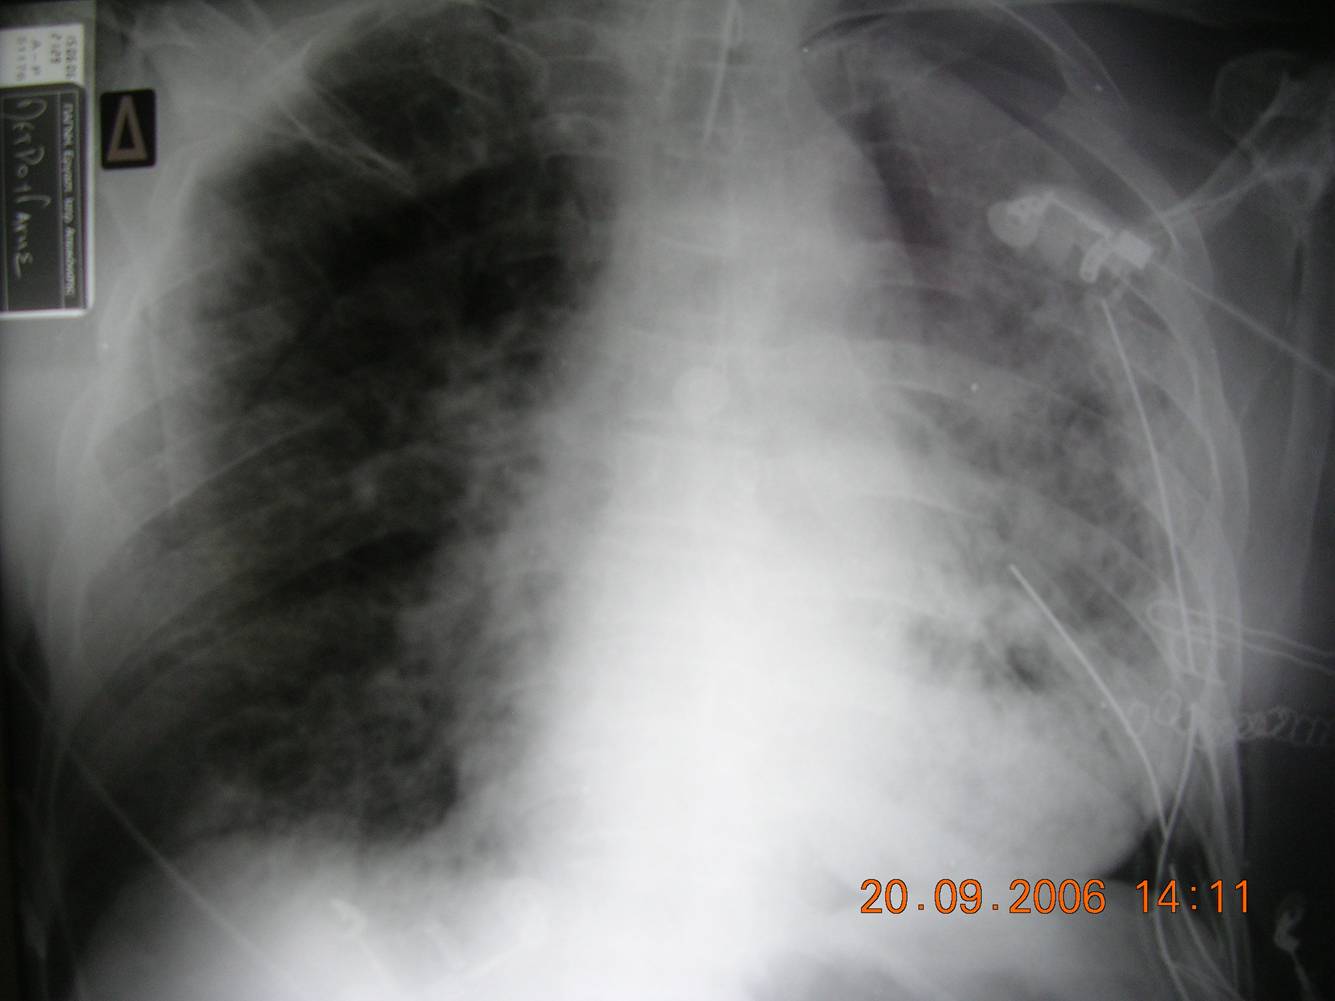

- Chest radiograph (Fig 1): Diffuse bilateral pulmonary infiltrates consistent with pulmonary edema.